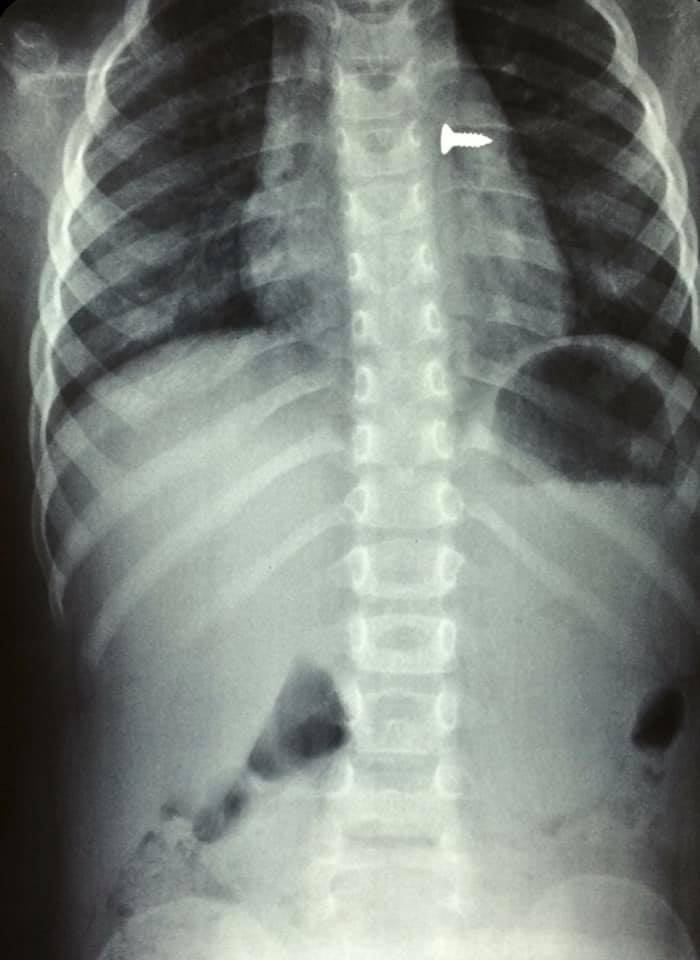

Η βίδα κατέληξε στον αριστερό πνεύμονά του Κòριτσιού και χρειάστηκε επείγουσα χειρουργική επέμβαση.

Την ίδια στιγμή έγιναν ακτινογραφίες οι οποίες έδειξαν πως η βίδα είχε ήδη φθάσει στον αριστερό πνεύμονα του παιδιού. Αμέσως οι γιατροί ξεκίνησαν χειρουργείο και κατάφεραν να αφαιρέσουν την βίδα.

Πολύ επείγον χειρουργείο! Πριν από λίγο. Αφαίρεση βίδας από αριστερό βρογχικό δέντρο τρίχρονου κοριτσιού. Πολύ επικίνδυνο…